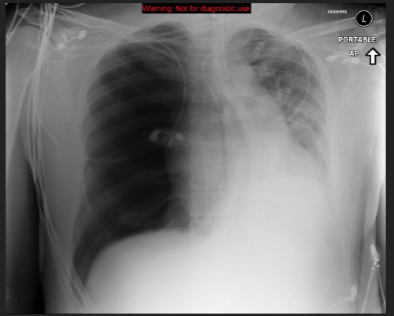

25

hemothorax